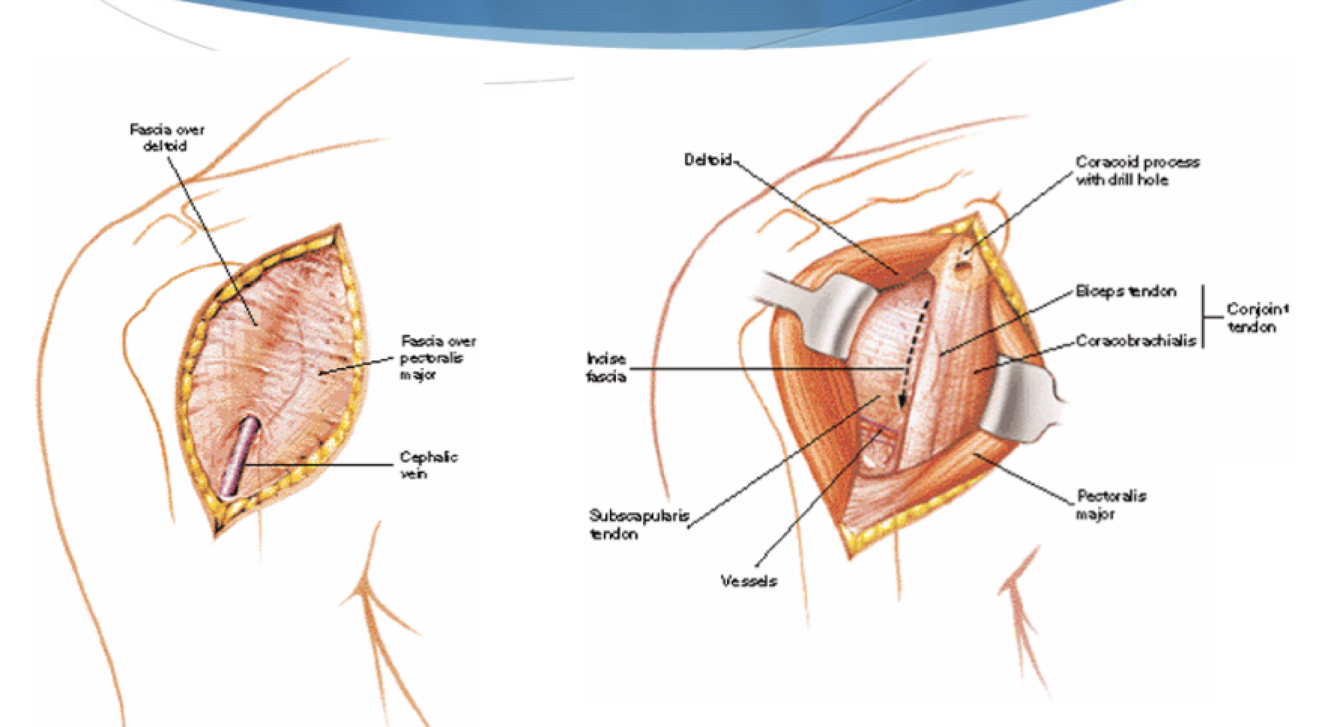

Deltopectoral

Interval: Deltoid (axillary n.) & pec major (med & lat pectoral n.)

- cephalic vein is landmark

Approach: Split deltoid and pec, incise clavipec fascia, come down on subscapularis

Dangers: cephalic vein, axillary n., musculocutaneous n. Biceps tendon, anterior circumflex vessels